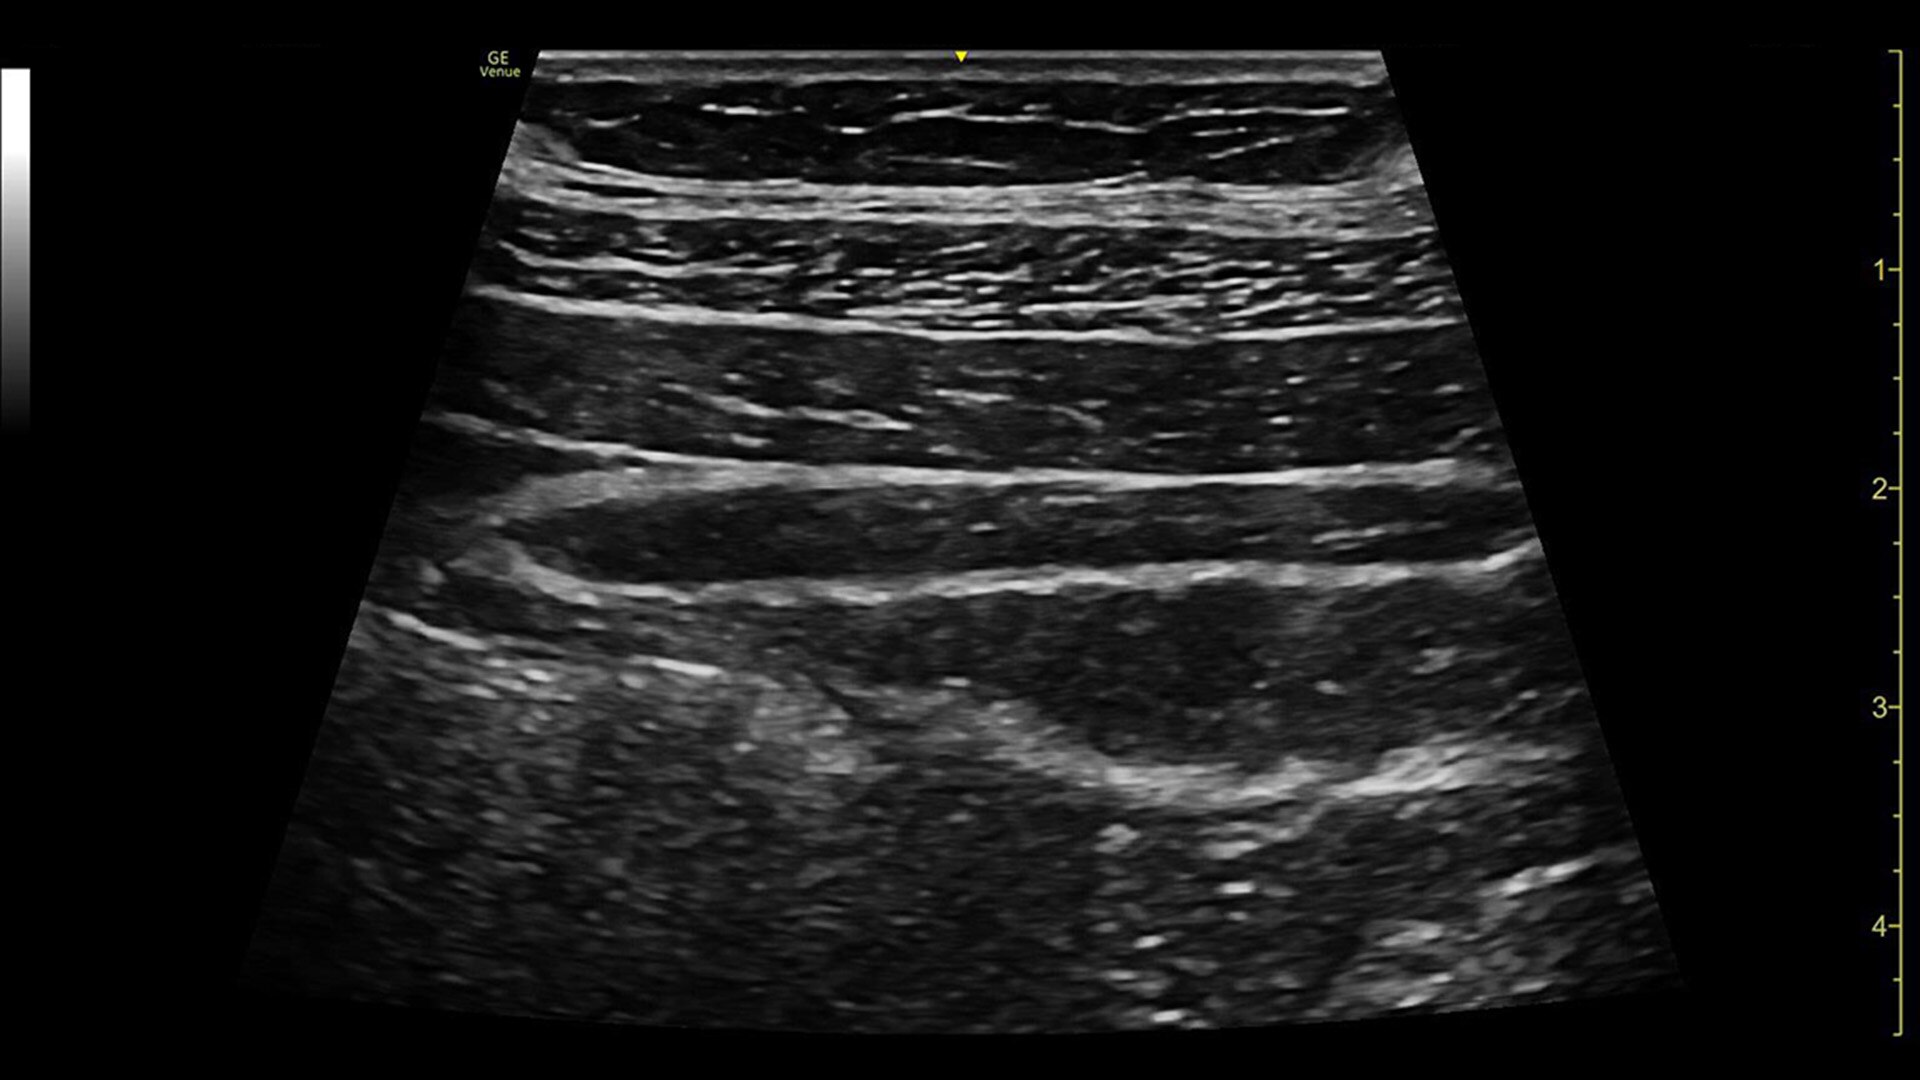

Visualize more anatomy in a single scan with Virtual Convex

This tool provides a wide field of view so users can visualize more large anatomy structures in a single scan while also aiming to enhance image quality on linear probes.